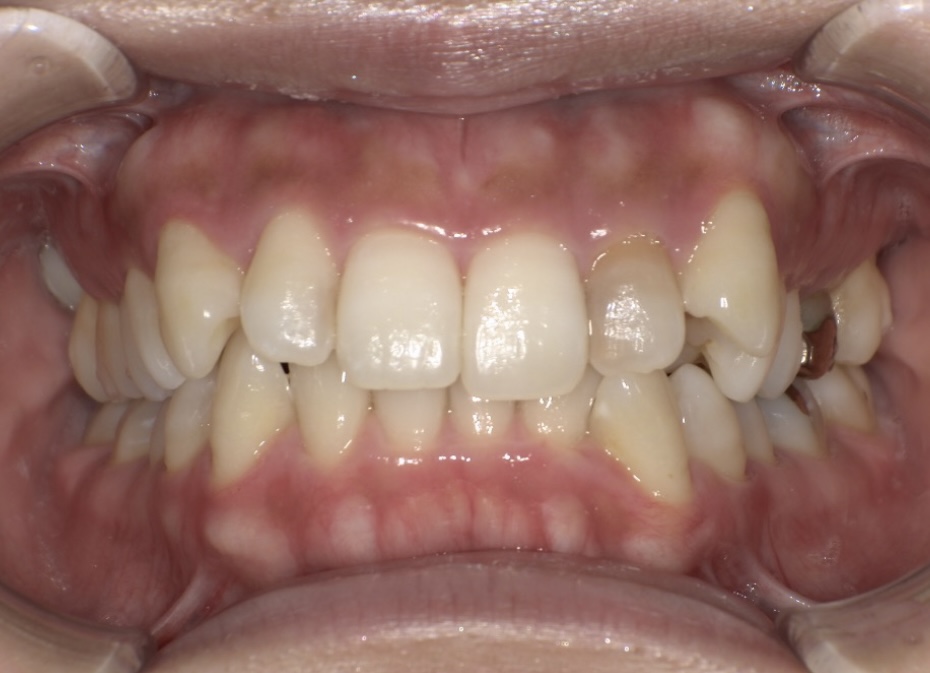

今回ご紹介するのは、前歯の出っ張り(上顎前突)とガタガタ(叢生)を気にされて来院された20代女性の患者様です。

最初に来られた際の写真です。上の前歯が前側にありますが内側を向いており、前歯の噛み合わせが深い状態であり、ガタガタもあります。